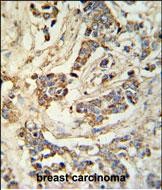

- MRAP Antibody (N-term) (Cat. #P30597) IHC analysis in formalin fixed and paraffin embedded breast carcinoma followed by peroxidase conjugation of the secondary antibody and DAB staining. This data demonstrates the use of the MRAP Antibody (N-term) for immunohistochemistry. Clinical relevance has not been evaluated.